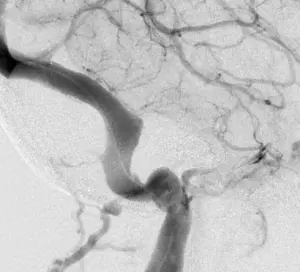

Intracranial venous stenosis prior to stent placement (above) and after (below)

For patients with pseudotumor cerebri resulting from intracranial venous stenosis, Liu and his colleagues at UVA are now utilizing endovascular venous stent placement with positive, longer-term results. According to Liu, this technique has slowly been gaining acceptance in the past decade, and UVA is working to prove that stent placement actually reduces a patient’s intracranial pressures.

“At UVA, we are proving that stent placement reduces pressure by utilizing a pressure monitor,” he says. “Before the procedure, we implant a monitor into the brain that transduces intracranial pressures and provides a baseline measurement. We then perform the procedure with the monitor in place. Even with patients on antiplatelet therapy, we have found that the added risk of placing an invasive monitor is almost negligible and is far outweighed by the benefit of being able to measure intracranial pressures in real time before, during and after stent placement.

“So far, we are seeing immediate results,” adds Liu. “In the past year, among those patients who have undergone concomitant pressure monitoring during stent placement, all have had their intracranial pressures return to normal within one to two hours after their procedure. This is the first time we have definitive and consistent proof that improving venous outflow with stent placement normalizes a patient’s intracranial pressures.”